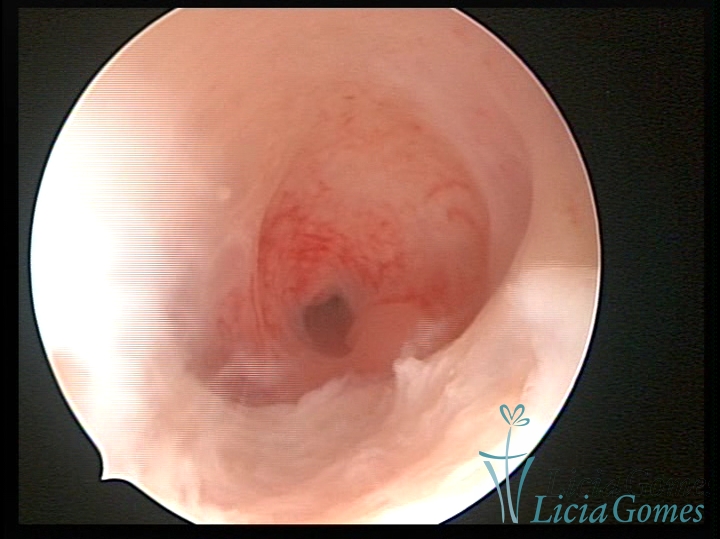

Septate uterus

It probably occurs by the lack of resorption on the middle line, in the merge of Müllerian ducts. The uterus is divided by a partial or total septum which is viewed as a crossbar, not covered by endometrium, which not bleeds when sectioned.

Complete septum when it occupies the whole extension of the cavity, dividing it into two hemicavities.

When this septum occupies only a part of the extension of the uterine cavity, it is considered as incomplete.